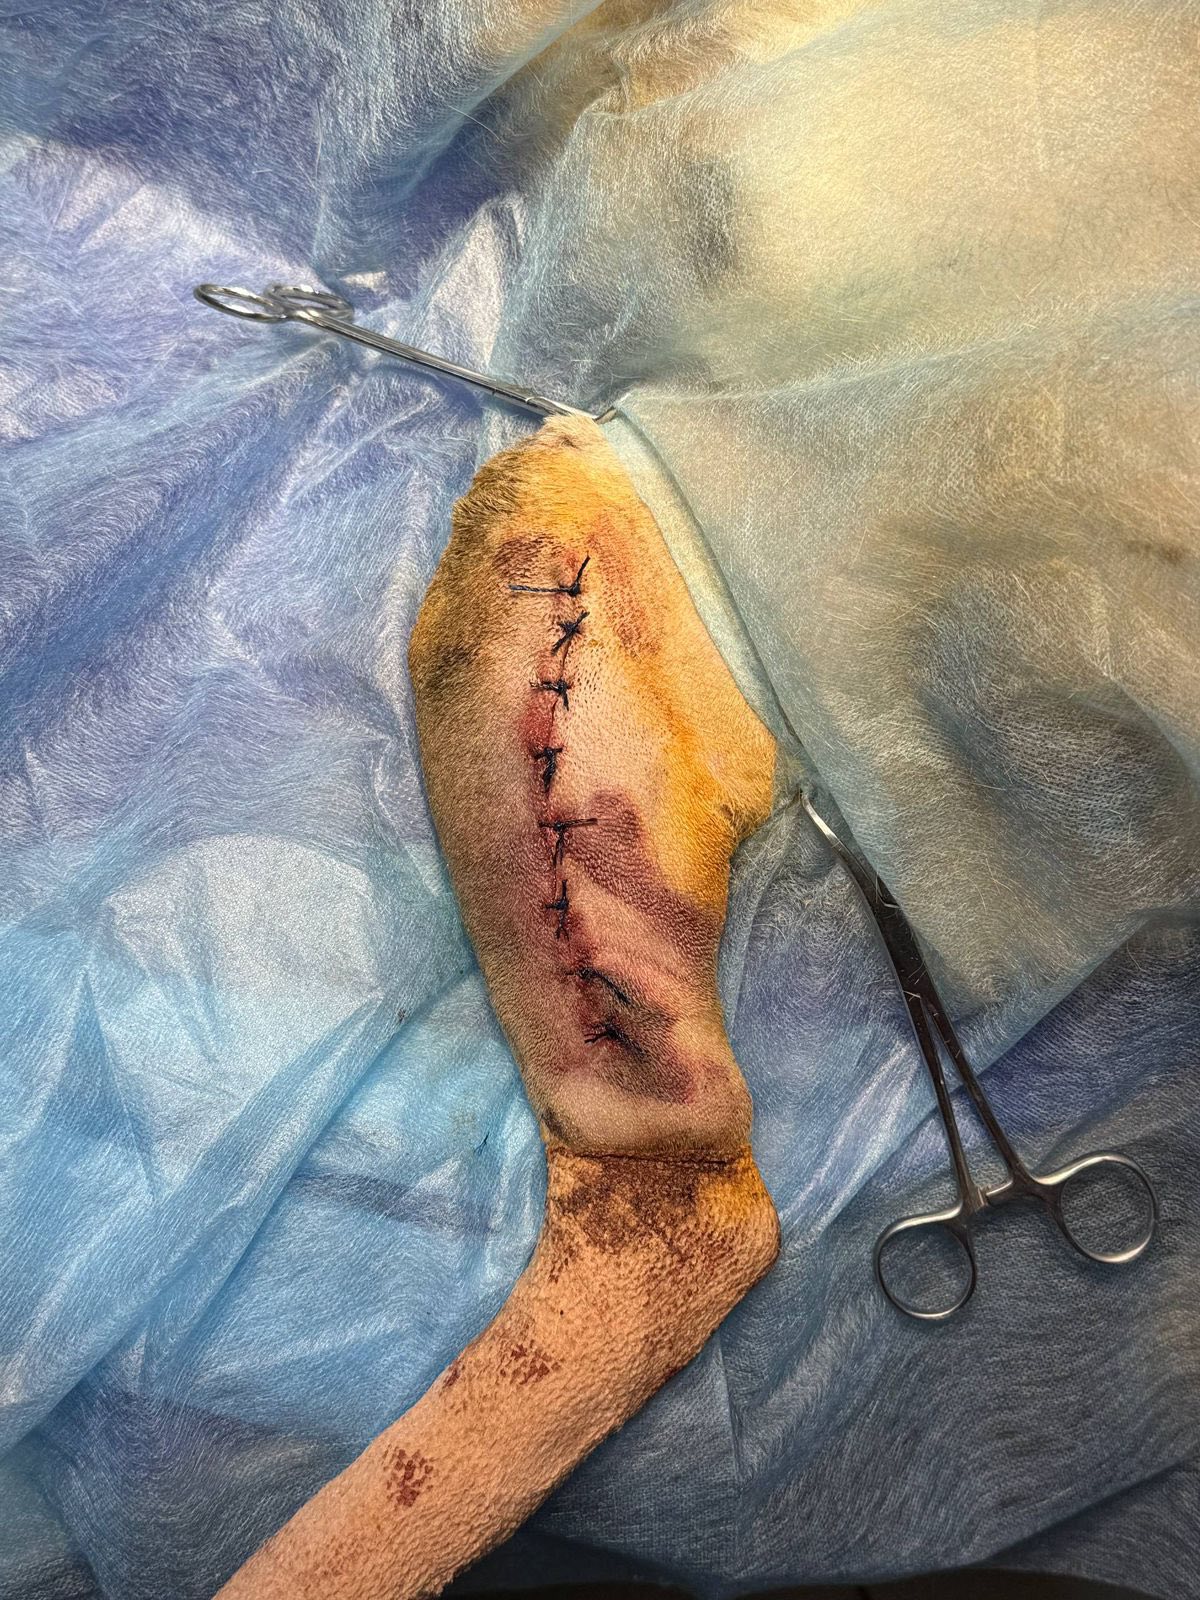

Ветеринары провели срочную операцию, которая прошла успешно.

Сейчас лапка заживает, а собачка постепенно восстанавливается и с каждым днем чувствует себя лучше.